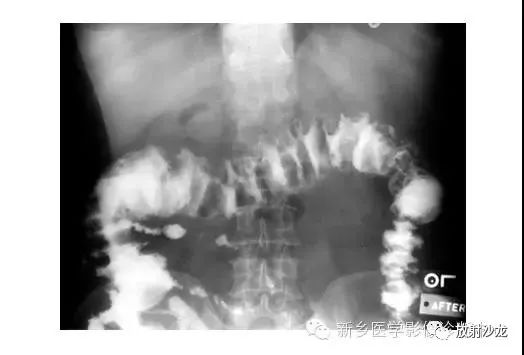

腹部平片解剖

腹部平片正常表现

腹部脏器有实质器官和空腔脏器之分,其正常腹平片表现不同。

● 腹平片上实质器官的正常表现:

实质器官:肝、胰、脾和肾等是中等密度,但借助于器官周围或邻近的脂肪组织和相邻充气肠胃的对比,于腹平片上,可显示器官的轮廓、大小、形状及位置。

正位片在部分病人可显示肝下缘,肝下缘与肝外缘相交形成肝角,一般呈锐角。

脾上极与左膈影融合,下极较圆钝。而肾沿腰大肌上部排列。

胰腺于平片上不易显示。子宫偶尔显影,位于膀胱上缘上方呈扁圆形软组织影。

● 空腔脏器在腹平片上的主要表现:

空腔器官:膀胱的脏壁为中、胆囊和肠胃道等密度,依腔内容物不同而x线表现不同。

胃、十二指肠球部及结肠内可含气体,于腹平片上可显示其内腔。小肠除婴幼儿可有积气外,一般充满食糜及消化液,与肠壁同属中等密度,因缺乏对比而不能显示。

如胃内有较多固态食物,结肠或直肠内有较多粪便,因为它们周围有气体衬托,故可显出软组织密度斑片或团块影。

结肠分布于腹部四周。膀胱和胆囊周围有较多脂肪,也可显示部分边缘。